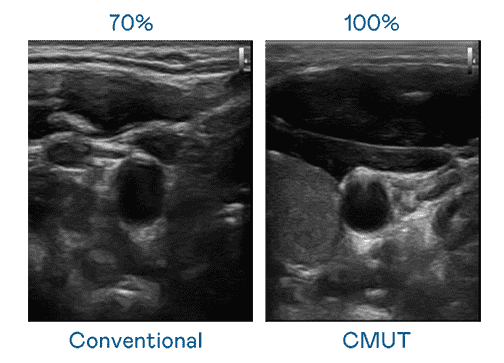

CMUT 技术是一种用电容式微机电元件来产生超音波讯号的技术。。。与传统 PZT 压电式技术相比,,,,CMUT 频宽增加 30%,,更宽频的超音波讯号让影像解析度大幅提升,,是实现高影像品质医疗超音波扫描、、、、促进精准医疗发展的关键技术。。。

大频宽带来超清晰影像

超音波影像的解析度高低,,,,首先取决于探头能发出的讯号频宽。。。。2121非凡 CMUT 可提供高清晰的超音波讯号,,提供高频宽、、高灵敏度、、、、影像纹理细节更高的超音波影像,,,,协助医护人员缩短影像判读时间及利用精准的医疗影像进行诊断。。。。